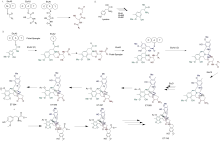

Biosynthesis

The biosynthesis of trabectedin in Candidatus Endoecteinascidia frumentensis starts with a fatty acid loading onto the acyl-ligase domain of the EtuA3 module. A cysteine and glycine are then loaded as canonical NRPS amino acids. A tyrosine residue is modified by the enzymes EtuH, EtuM1, and EtuM2 to add a hydroxyl at the meta position of the phenol, and adding two methyl groups at the para-hydroxyl and the meta carbon position. This modified tyrosine reacts with the original substrate via a Pictet-Spengler reaction, where the amine group is converted to an imine by deprotonation, then attacks the free aldehyde to form a carbocation that is quenched by electrons from the methyl-phenol ring. This is done in the EtuA2 T-domain. This reaction is done a second time to yeid a dimer of modified tyrosine residues that have been further cyclized via Pictet-Spengler reaction, yielding a bicyclic ring moiety. The EtuO and EtuF3 enzymes continue to post-translationally modify the molecule, adding several functional groups and making a sulfide bridge between the original cysteine residue and the beta-carbon of the first tyrosine to form ET-583, ET-597, ET-596, and ET-594 which have been previously isolated.[17] A third O-methylated tyrosine is added and cyclized via Pictet-Spangler to yield the final product.[17]

Total synthesis

The total synthesis by E.J. Corey [18] used this proposed biosynthesis to guide their synthetic strategy. The synthesis uses such reactions as the Mannich reaction, Pictet-Spengler reaction, the Curtius rearrangement, and chiral rhodium-based diphosphine-catalyzed enantioselective hydrogenation. A separate synthetic process also involved the Ugi reaction to assist in the formation of the pentacyclic core. This reaction was unprecedented for using such a one pot multicomponent reaction in the synthesis of such a complex molecule.